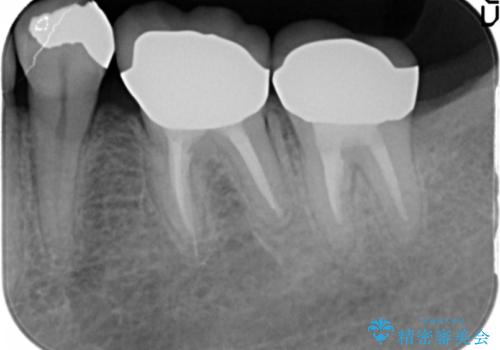

- 低予算で銀歯を白くしたいとご希望し来院された患者様です。

右上小臼歯(右上5)はオールセラミッククラウン(e-max press)、下顎臼歯(下顎両側67)はメタルボンドクラウンによりやりかえることにしました。

再根管治療はご希望されず、行っておりません。

右上小臼歯(右上5):オールセラミッククラウン エコノミー

下顎両側臼歯(下顎両側67):メタルボンドクラウン エコノミー